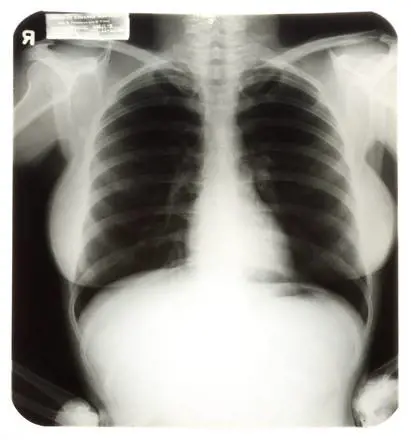

Morto perché operato al polmone sbagliato a causa di una tac letta al contrario. Questa l'incredibile ricostruzione sulla base della quale tre medici della Ulss 3 di Bassano del Grappa sono accusati di omicidio colposo per la morte del 67enne Gioachino Lessio.

Lessio, geometra originario della Valbrenta, era deceduto dopo tre quarti d'ora di tentativi di rianimazione in seguito a un intervento chirurgico di toracentesi, per il drenaggio dei polmoni. I parenti, da subito, avevano espresso il sospetto che si trattasse di un errore clamoroso: l'uomo sarebbe stato operato al polmone sbagliato. E del resto anche il direttore generale dell'Ulss, Antonio Compostella aveva parlato del "sospetto di aver effettuato la procedura di toracentesi dal lato opposto a quello interessato dalla patologia" sin dai giorni successivi all'operazione.

A seguito dell'inchiesta avviata dalla procura della Repubblica, il medico legale Antonio Cirnelli ha depositato conclusioni che delineano un quadro davvero paradossale: i medici avrebbero letto la lastra al rovescio, operando il polmone sano invece di quello

malato. Il paziente sarebbe così morto in meno di dieci minuti per l'asfissia provocata dall'errore.